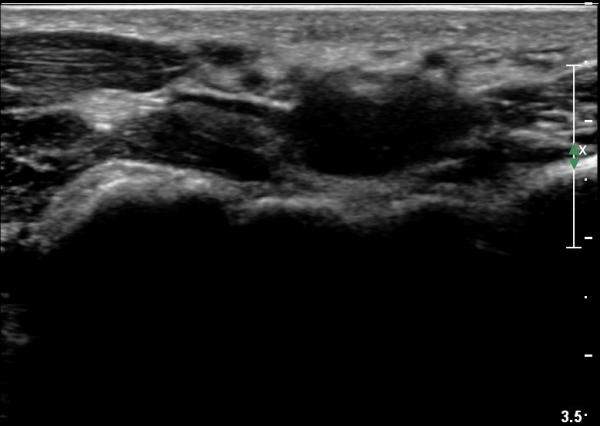

ÃÊÀ½ÆÄ °Ë»ç

¼Õ¸ñÀÇ È¾´Ü¸é°Ë»ç¿¡¼­ Á¤Á߽ŰæÀÇ ºÎÁ¾ µî ƯÀÌ ¼Ò°ßÀÌ º¸ÀÌÁö ¾Ê´Â´Ù(»çÁø 1).